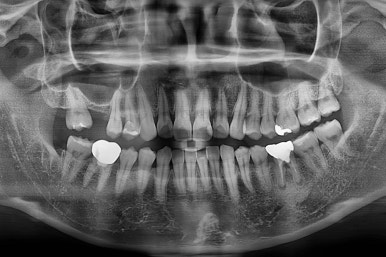

X-ray로 봤을 때 빈 공간에는 여러 가지 문제가 있었는데요.

뒷니가 쓰러졌다.

공간이 잠식 당했다.

어금니 위쪽 공기주머니가 잇몸뼈를 갉아먹으면서 잇몸뼈가 매우 얇아져있다.

진행상황을 X-ray로도 확인해 줍니다.

어금니도 원위치로 많이 갔네요.

적절한 공간 확보 이후 해당 부분의 뼈가 너무 얇아 임플란트를 하기에 부적절했던거죠.

상악동 거상술 + 골이식을 광범위하게 꽤 많은 양을 하고, 한참을 기다립니다.